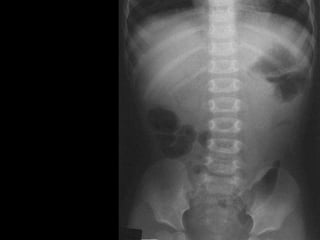

Plain x-ray abdomen

• May be normal.

• Meniscus sign:

• Crescent of gas within colonic lumen that

outlines the apex of intussusceptum.

• Little air in small intestine.

Meniscus

sign

Plain x-ray abdomen • May be normal. • Meniscus sign: • Crescent of gas within colonic lumen that outlines the apex of intussusceptum. • Little air in small intestine.